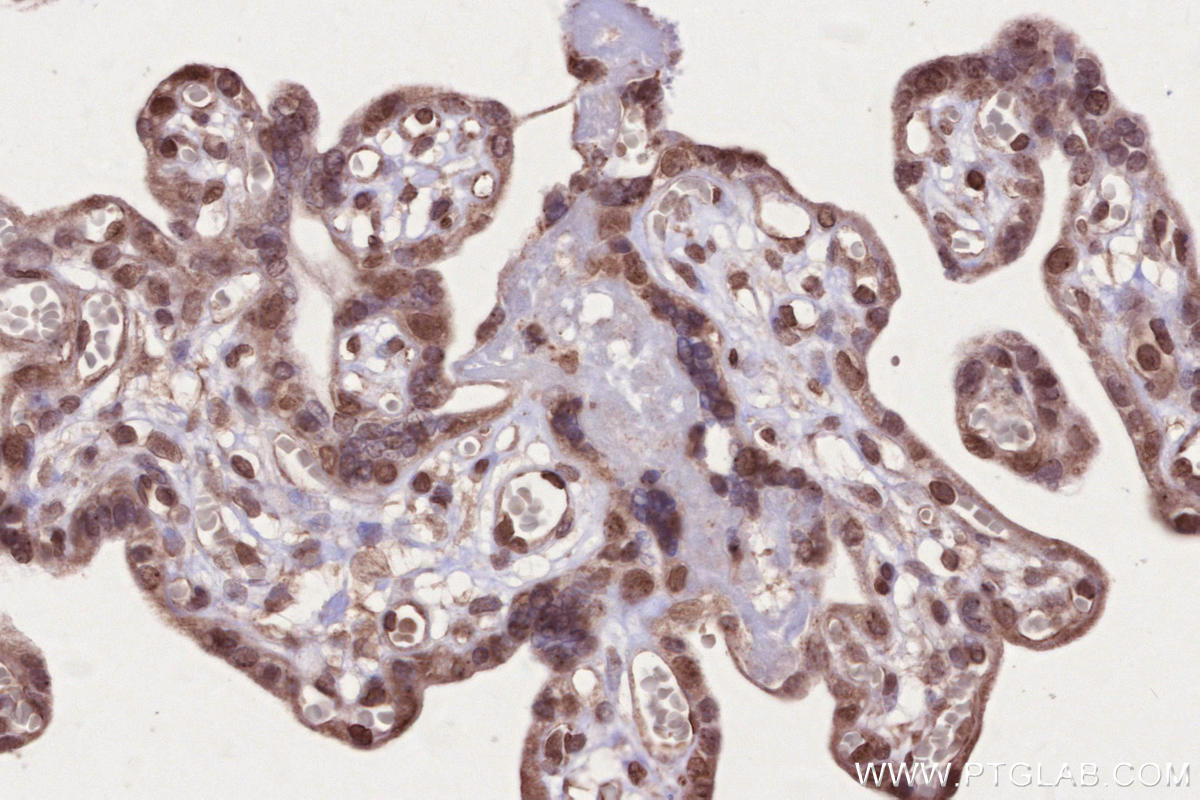

Validation Data Gallery